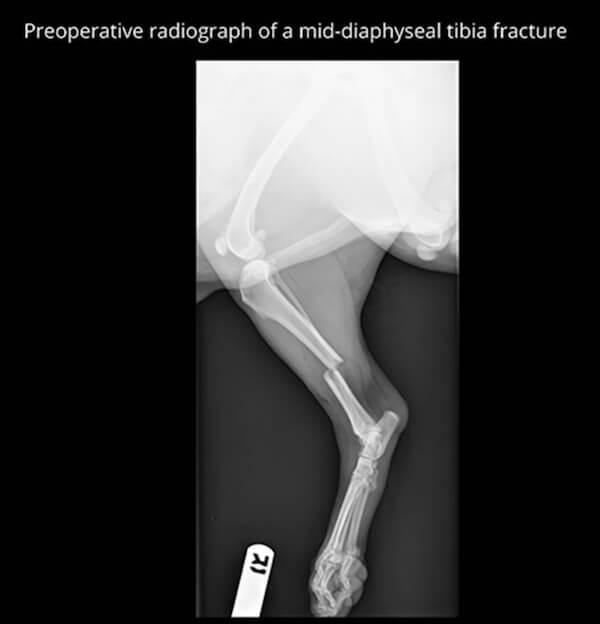

Each fracture is evaluated individually using digital imaging, and treatment plans are tailored to the type of fracture, the pet's age, size, activity level, and overall health. Surgical repair may involve pins, plates, screws, or other stabilization methods to promote proper healing.